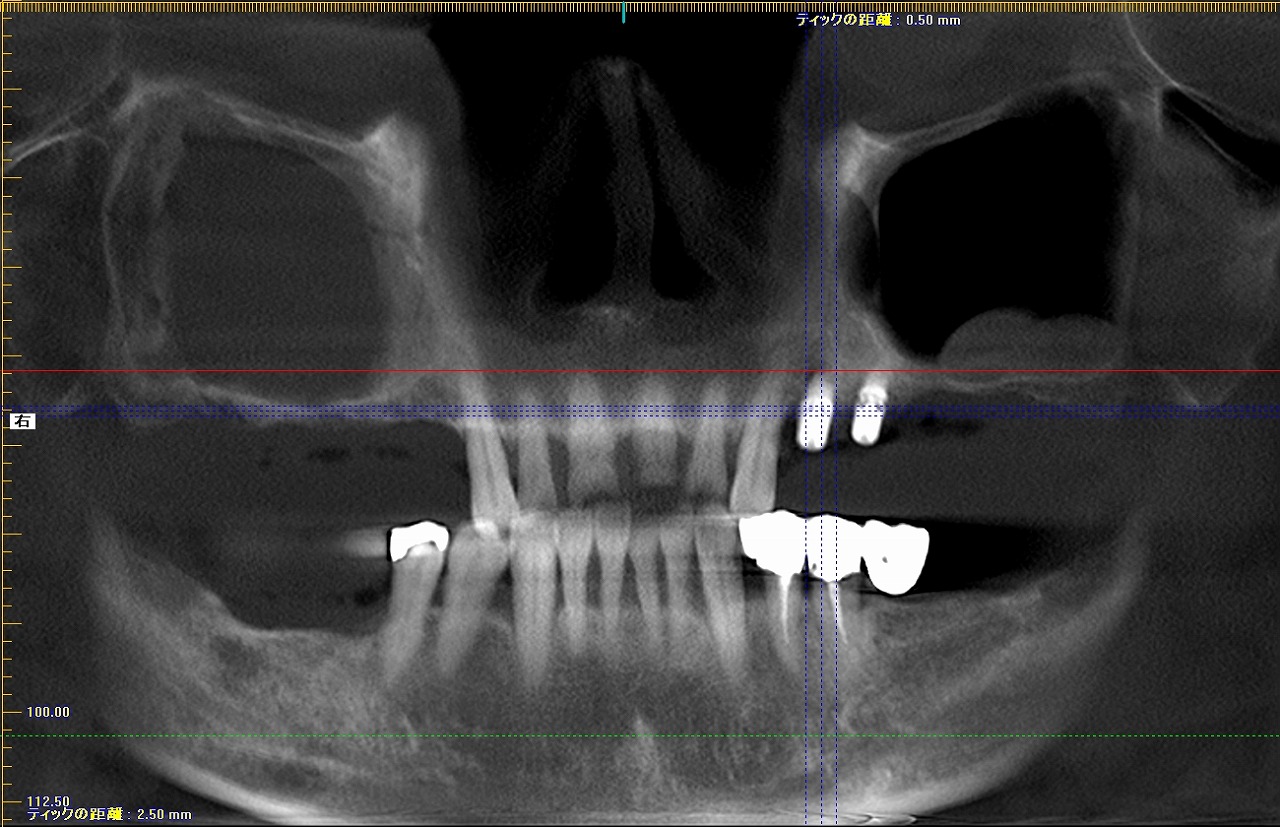

傾斜埋入ケース。 難ケース。| |広島市安佐南区の歯科医院 傾斜埋入ケース。 難ケース。 トップ お知らせ・ブログ 傾斜埋入ケース。 難ケース。 傾斜埋入ケース。 難ケース。 Web診療予約 初めての方へ 選ばれ続ける理由 院内設備について 歯が痛いしみる一般歯科 歯がぐらぐらする歯周病 健康な歯を保ちたい予防歯科 子供の虫歯予防をしたい小児歯科 銀歯をセラミックに審美歯科 白い歯を目指しませんか?ホワイトニング 矯正専門医がいるので安心矯正歯科 抜けた歯を補いたいインプラント・入れ歯 医院案内 スタッフ紹介 メリィハウス歯科クリニックオフィシャルホームページ ラベンダー歯科クリニックオフィシャルホームページ お知らせ・ブログ ホーム 診療科目 一般歯科 歯周病治療 予防治療 小児歯科 審美治療 ホワイトニング 矯正歯科 入れ歯・インプラント マウスピース矯正 初めての方へ 院長・スタッフ 設備紹介 医院案内・アクセス メニューを閉じる